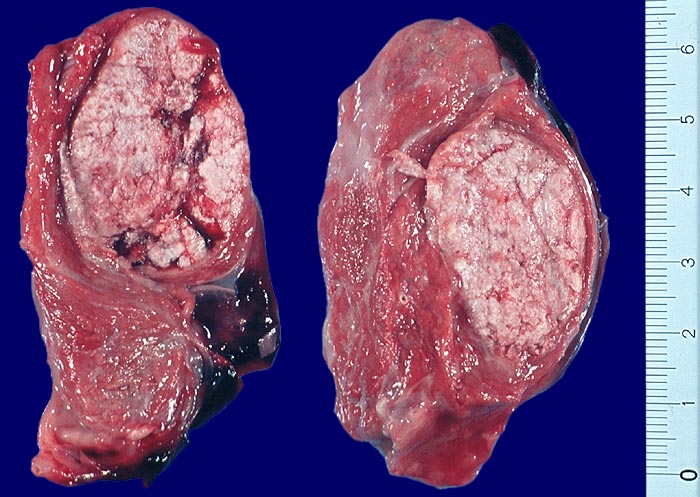

• Anschnitt eines grossen mikrofollikulären Knotens (autonomes Adenom) mit angedeuteter Kapsel und zentraler Einblutung. Oben zwei weitere kleine Satellitenknoten.

• Kompression des angrenzenden Schilddrüsenparenchyms. Dieses besteht aus grossen Follikeln mit kubischem oder abgeflachtem Epithel und reichlich kompaktem dunklem Kolloid in den Follikellumina.